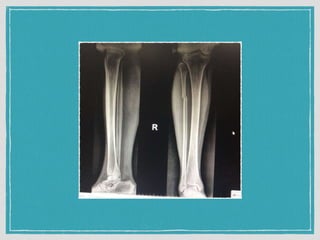

Close isolated fracture of Right proximal 1/3 fibular

on short leg slab

Refer R/o compression fractureL1 Close isolated fracture of Right proximal 1/3 fibular on short leg slab